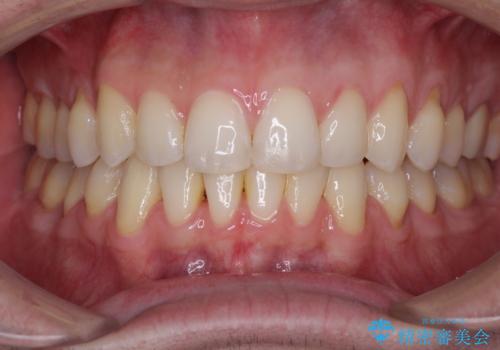

見た目の改善はもちろんですが、ものが挟まらなくなったり、舌触りが良くなったりと、口腔内の状態が改善されました。